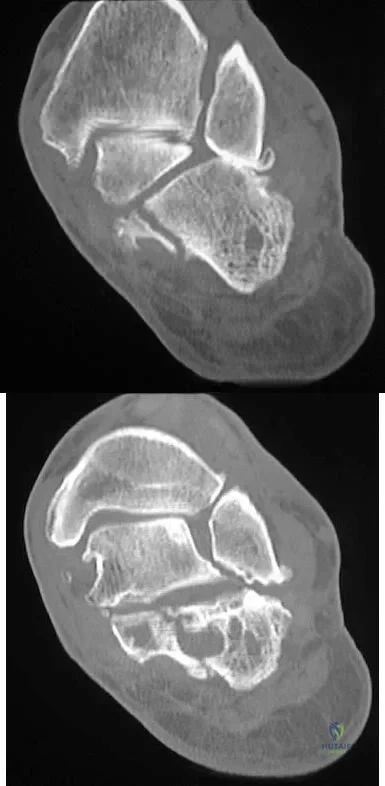

A 15-year-old boy has hindfoot pain and very limited subtalar motion. A CT scan reveals a talocalcaneal coalition involving 40% of the middle facet. He has no degeneration of the posterior subtalar facet. Following failure of nonsurgical management, treatment should consist of

Explanation